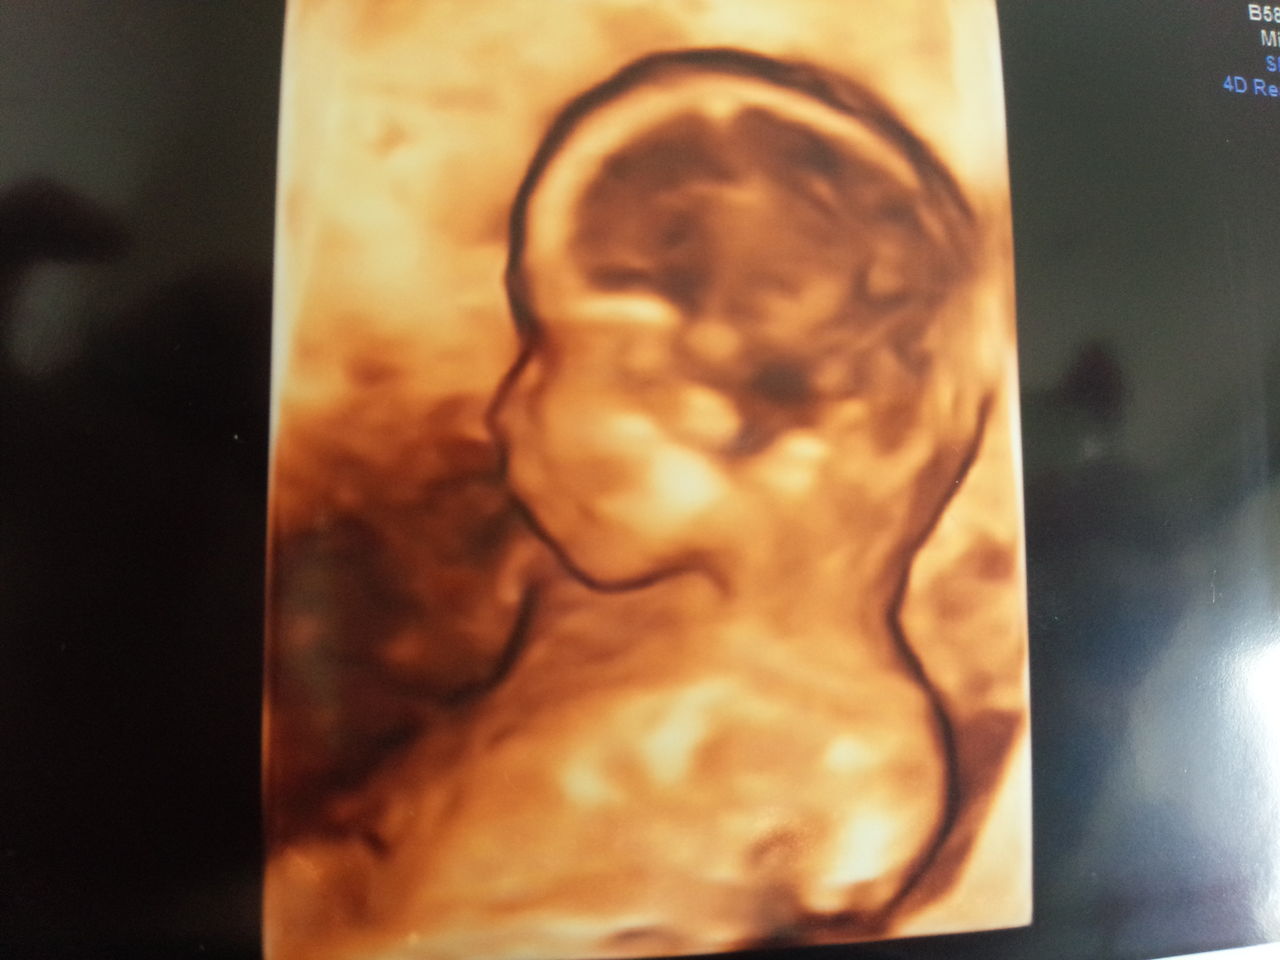

赤ちゃんの3d 4dエコー写真 実際の顔と比較してみたら似てた 旅するダンサー自由記

3dエコーはいつから 性別がわかる 写真の見方 料金 実際の顔との違いについて ままのて

医療監修 エコー写真を妊娠の経過別に紹介 写真の見方や性別の見分け方 ママリ

元助産師ママが解説 エコー写真の意味と 性別 の見分け方 2017年9月1日 ウーマンエキサイト 1 2